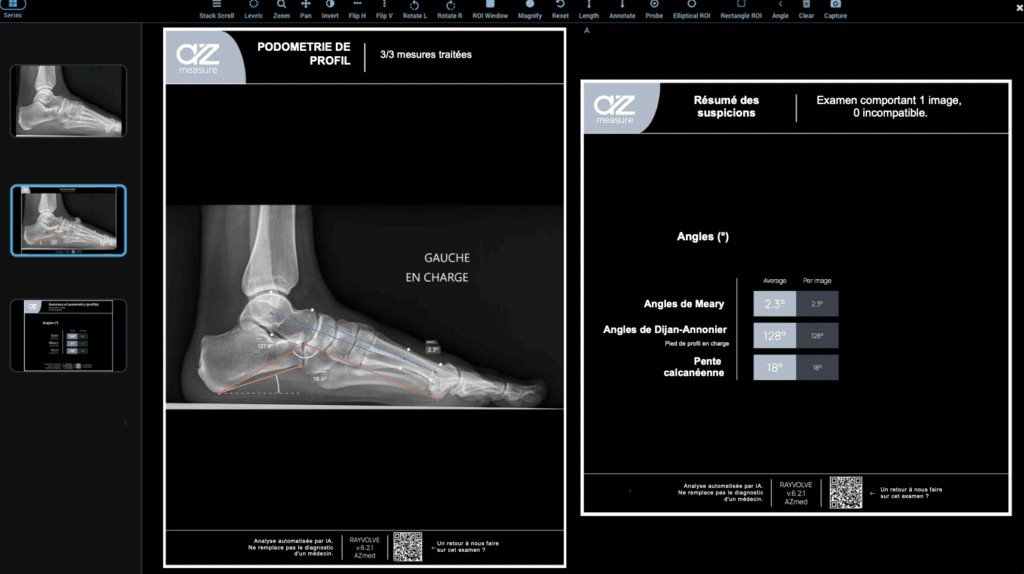

- AZmeasure : réalisation automatique des mesures ostéo-articulaires (podométrie, pangonométrie, coxométrie, rachis).